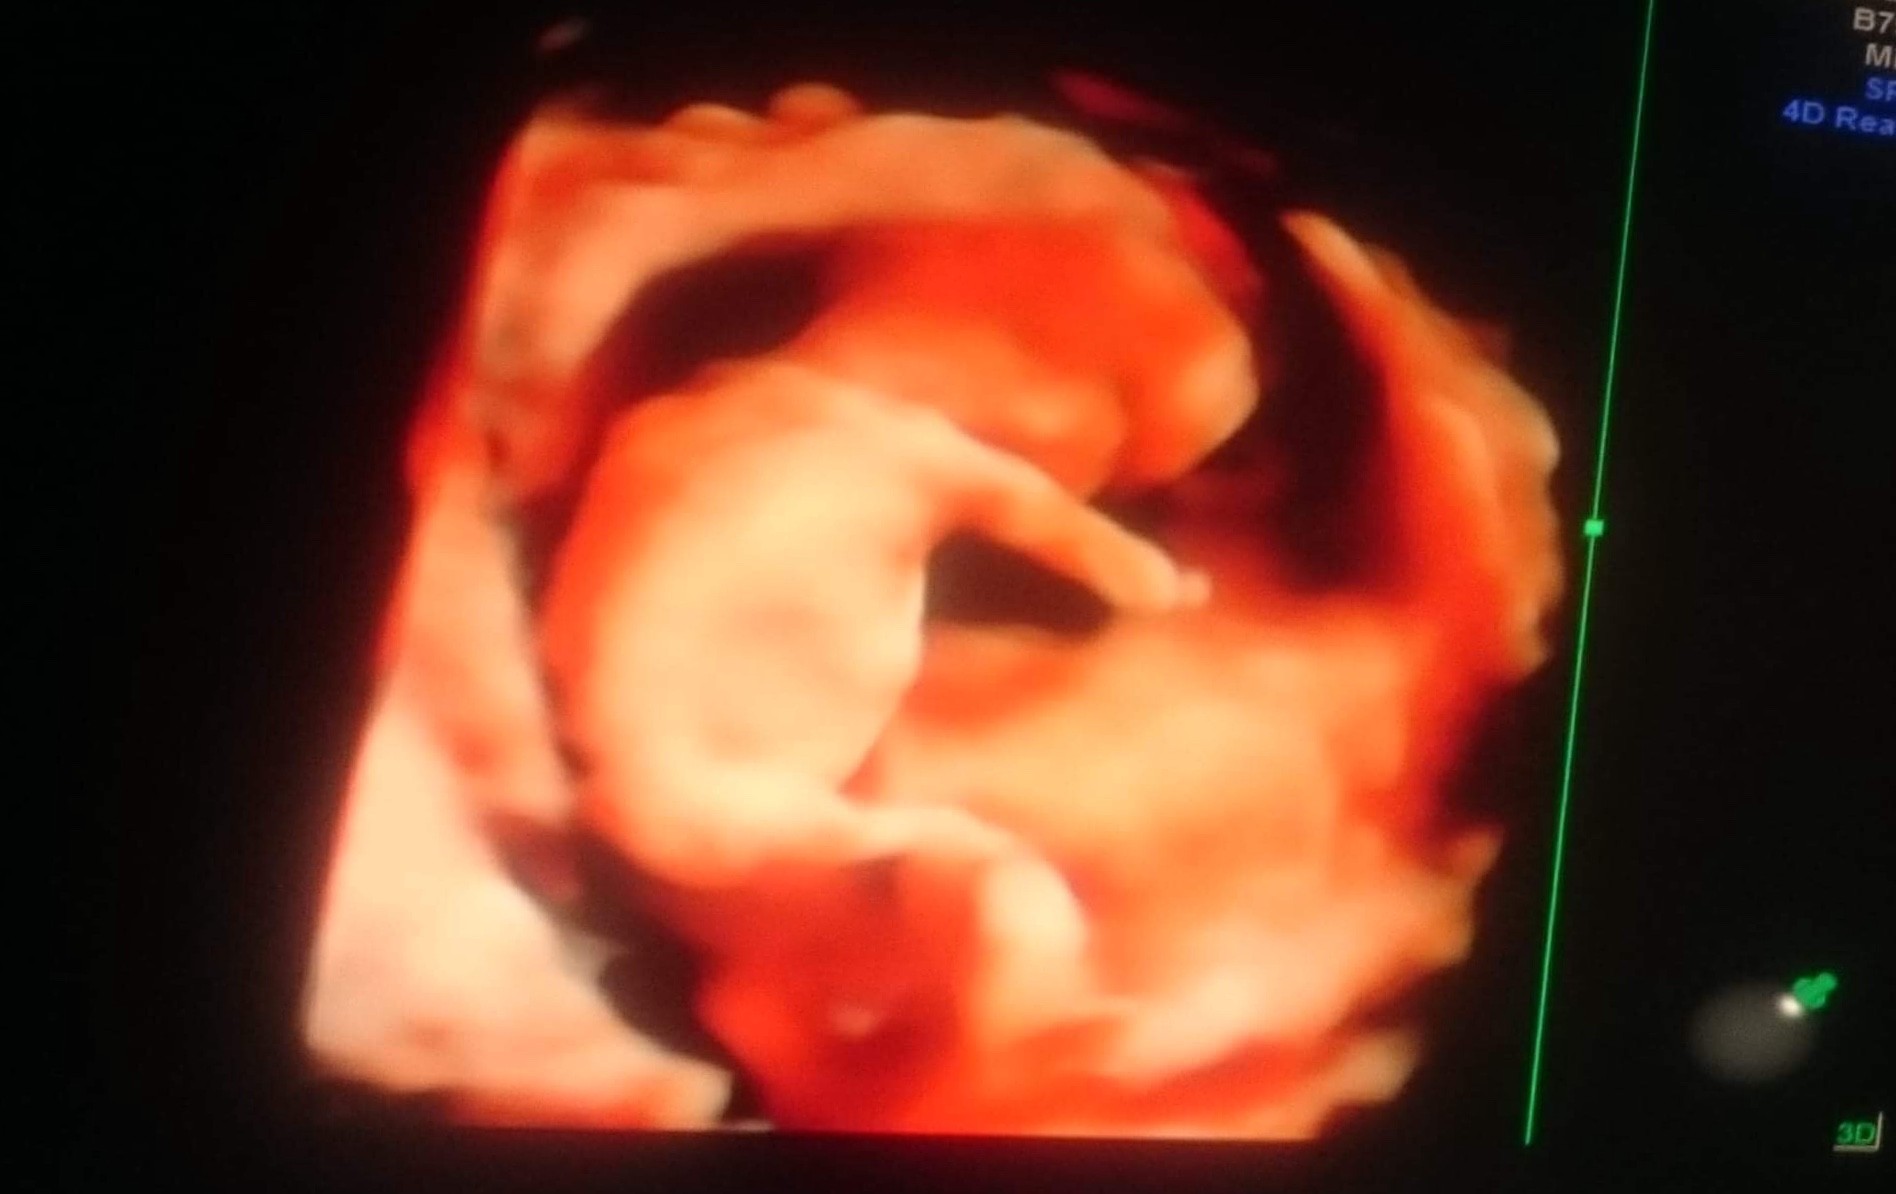

Zobacz załącznik 858157 Wczoraj byłam na wizycie - dziecko waży ok. 99 g ;p Wszystko w porządeczku ;) Zmieniłam lekarza - zapisałam się już po pierwszej wizycie do niego, ale musiałam czekać prawie 2 miesiące, więc byłam jeszcze na jednej wizycie w u mojej poprzedniej ginekolog. Jestem bardzo zadowolona ze zmiany ;) Nawet na prenatalnych tak dokładnie wszystkiego nie sprawdzał i tyle nie opowiadał co ten wczoraj ;)